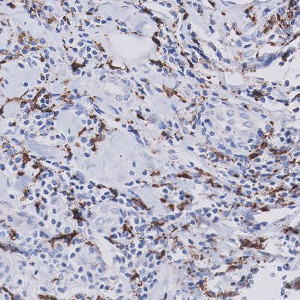

Figure 1

Breast tissue with CD68 positive nuclei.